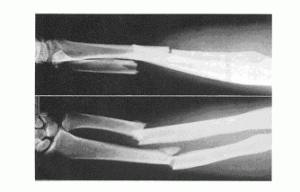

「先生、橈骨尺骨の骨幹部骨折後、橈尺骨の離解を主治医から懸念されています。後遺障害はどうなるのでしょうか?」

これにすらすら答えなければ信頼は得られません。実際に某弁護士事務所で「それってどこの骨?」って聞き返されて失望した被害者さんもいました。やはり弁護士先生とはいえ、医療全般に精通しているわけではありません。数か月勉強してきたた被害者さんの知識が上回ってしまうのです。